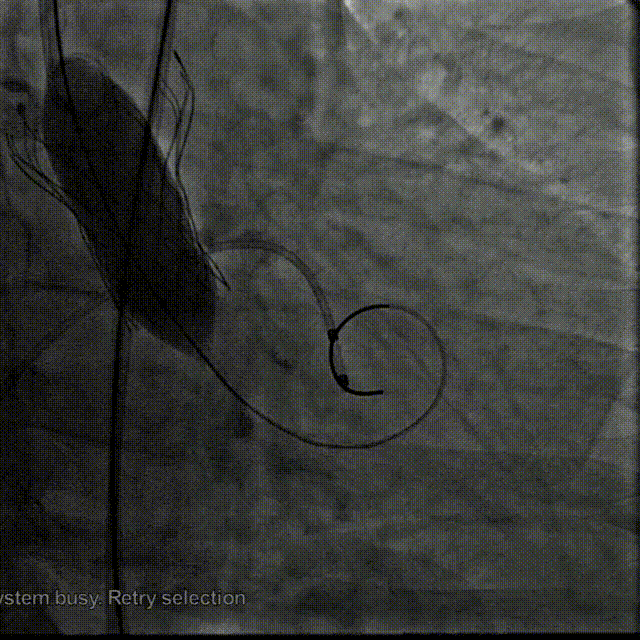

TaurusElite 输送器轻松过弓、跨瓣,TaurusElite AV26瓣膜高位释放。

TaurusElite轻松过弓

瓣膜释放